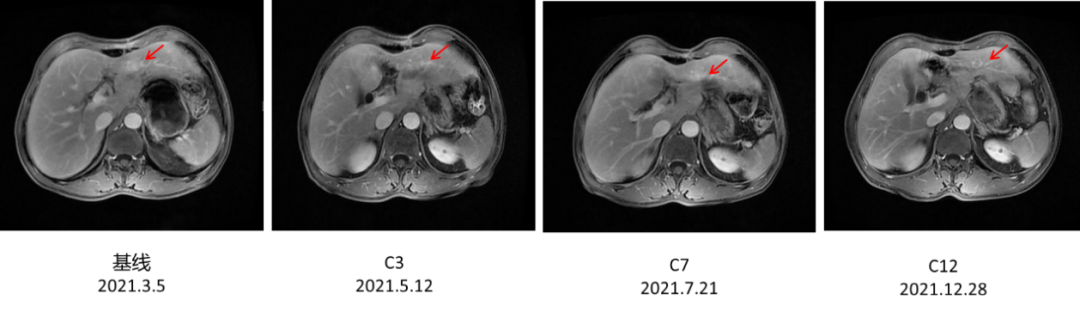

▌病例作者:大连医科大学附属第一医院 李颖 教授 ▌点评专家:大连医科大学附属第一医院 张洁 教授 编者按 ●我国是胃癌大国,根据世界卫生组织国际癌症研究机构(IARC)发布的2020年中国最新癌症负担数据:2020年中国癌症新发病例457万例,其中胃癌48万例位居第三;2020年中国癌症死亡人数300万,其中胃癌37万,位居第三[1]。70%的胃癌患者确诊时为局部进展期或进展期胃癌。其中HER2阳性胃癌是一类高度异质性肿瘤,侵袭性强、复发率高、预后不良。国内胃癌HER2阳性率的多中心研究结果显示,中国人群胃癌HER2阳性率为12~13%。ToGA[2]研究证实,曲妥珠单抗联合化疗能显著提高HER2过表达晚期胃癌患者治疗反应率,改善患者生存状况,因此曲妥珠单抗被推荐用于HER2过表达晚期胃癌的一线治疗。肝脏是胃癌血行转移最常见的靶器官,胃癌肝转移的总体发生率约9.9%~18.7%。本文通过一例赫赛汀®转换为汉曲优®治疗HER2阳性晚期胃癌伴肝转移的病例,向大家介绍汉曲优®(曲妥珠单抗)在治疗HER2阳性晚期胃癌伴肝转移患者的临床获益情况。(注:本文中汉曲优®为复宏汉霖研发生产的曲妥珠单抗) 病史简介 患者:王某,64岁,男,身高180cm ,体重60kg ,BMI 18.52。 主诉:胃癌姑息术后1年余。 既往史:既往体健,否认吸烟史、饮酒史。 家族史:否认家族性遗传病、传染史。 查体:全身皮肤粘膜无黄染,全身浅表淋巴结不大,腹部可见手术瘢痕,质软,无压痛,肝脾肋下未及,未触及包块,移动性浊音阴性。 ▌影像学检查: 2021年1月21日腹部CT:胃窦癌征象,伴胃周、腹膜后增大淋巴结,请结合临床;肝右叶肝内胆管结石或钙化灶;左侧肾上腺强化不均。 图1.腹部CT 2021年1月22日胃镜示:胃窦环幽门见一溃疡型病变,致管腔狭窄,镜身无法通过。 图2. 胃镜 ▌肿瘤基本病理: 2021年1月25日:全麻下腹腔镜姑息性远端胃大部分切除D2廓清 B-Ⅱ+Braun消化道重建肝部分切除术。术中见:肝左外叶见1枚约1*0.5cm灰白结节,肿瘤位于胃下部,大小8*6cm,侵及胰腺被膜,NO.6组淋巴结肿大。 ▌胃术后病理: 胃溃疡型中低分化管状腺癌,大小4.7*3.7cm,侵及全层,脉管癌栓,神经侵犯;纤维脂肪组织内见淋巴结转移一枚,送检(6、7.8a、9组)淋巴结见转移癌(5/17),并见癌结节一枚。送检(1.3组、4sb组)淋巴结未见转移癌(0/6)。 ▌免疫组化: GST-π:(+),HER-2:(3+),Ki67:(+80%),MLH-1:(表达),MSH-2:(表达),MSH-6:(表达),PMS-2:(表达),P53/ target=_blank class=infotextkey>P53:(突变型)。 ▌肝术后病理: 肝内见中分化管状腺癌,大小为0.9*0.6*0.7cm,结合病史及免疫组化结果考虑为胃腺癌转移来源,累及肝被膜,未见明确脉管及神经侵犯。免疫组化:ARGINASE-1(-)、CDX-2(少许+),CK19(+)、CK20(-)、CK7(+)、GPC-3(部分+)、Hep-par(少许+)、Ki67:(+75%)、muc-5AC(+)、SATB2(-)、villin(+)。 ▌术后病理: 胃溃疡型中低分化管状腺癌淋巴结转移(图3左),肝内见中分化管状腺癌考虑为胃腺癌转移来源(图3右)。 图3 术后病理 诊断:胃癌姑息术后(pT3N2M1)PLVN+、Her-2过表达、pMMR型,同时性肝转移癌术后,肝转移癌(肝左叶单发)。 治疗经过 2021年1月25日:全麻下腹腔镜姑息性远端胃大部分切除 D2廓清 B-Ⅱ+Braun 消化道重建肝部分切除术。 2021年3月5日术后化疗时上腹部增强MRI发现疾病进展,出现新发肝转移癌。MRI示:胃体积减小,肝脏局部体积减小,肝左叶见一类圆形轻度环形强化影,平扫显示不清,最大径约16.6mm。诊断建议:肝、胃术后改变,肝左叶环形强化影,新发肝转移。(图4) 图4. 上腹部增强MRI 2021年3月3日起行一线曲妥珠单抗联合AS方案化疗: 具体:赫赛汀®:440mg 首周期剂量,360mg 后续周期剂量,7周期,因经济原因和患者体重下降原因调整为汉曲优® 300mg 继续完成后续治疗,目前共完成靶向治疗17周期(汉曲优®10周期);白蛋白紫杉醇:400mg,d1,ivgtt;TS-1:50mg,d1-14,bid,po,Q21d;完成治疗6周期;TS-1:60mg, d1-14,bid,po,Q21d;维持治疗,完成维持治疗8周期。 ▌治疗后影像学: 2021年5月12日、7月21日和12月28日:上腹部MRI示:肝、胃术后改变,肝左叶环形强化影,体积较前逐渐减小(最大径分别为15.8mm、14.8mm、10.6mm)。(图5) 图5.上腹部MRI ▌治疗后评价: PR ▌后续治疗方案: 后续患者沿用曲妥珠单抗(汉曲优®)联合替吉奥至今。 ▌病例小结: HER2阳性胃癌是一类独特的疾病亚型,其异质性高的特点要求在治疗时需要采用不同的策略与方法。在该病例中患者确诊为HER2阳性晚期胃癌伴肝转移。ToGA [2]研究证实,曲妥珠单抗联合化疗能显著提高HER2过表达晚期胃癌患者治疗反应率,改善患者生存状况,因此曲妥珠单抗被推荐用于HER2过表达晚期胃癌的一线治疗。该患者姑息性远端胃大部分切除D2廓清B-Ⅱ+Braun消化道重建肝部分切除术后5周行一线曲妥珠单抗联合AS方案化疗时再次发现肝转移病灶。使用赫赛汀®7周期,期间于2021年5月12日、2021年7月21日复查上腹部MRI肝左叶环形强化影,体积较前逐渐减小。 汉曲优®Ⅲ期临床研究[3]结果显示,汉曲优®与原研曲妥珠单抗疗效等效,安全性、免疫原性相似,曲妥珠单抗生物类似药得到NCCN-GI指南、CSCO-GI指南的用药推荐,2020年《中国生物类似药专家共识》也指出:生物类似药与参照药疗效等同、安全性相似,临床上可以替代使用。在本病例中,患者综合经济因素等原因,在使用原研曲妥珠单抗7周期有效后,转换为曲妥珠单抗生物类似药(汉曲优®)继续治疗,目前已使用10周期,并于2021年12月28日复查上腹部MRI示:肝、胃术后改变,肝左叶环形强化影,体积较前逐渐减小,达到PR,显示出良好的疗效和安全性。 专家点评 曲妥珠单抗联合治疗成为晚期HER2阳性胃癌的金标准 胃癌是全球第三大癌症相关死亡原因[1]。尽管在预防、早期发现和各种治疗选择方面有所改进,但预后仍然很差。胃癌诊断时通常已是晚期,生存期不到1年。化疗作为晚期肿瘤治疗的主要手段并没有明显的优势,这凸显了寻找新的更有效的治疗方案的必要性。基于目前对分子和细胞机制的了解,引入了一些新的生物学方法,如抗体疗法,用于治疗癌症,这些方法主要影响免疫系统或在癌症和转移发展中发挥作用的靶信号通路。在胃癌的治疗靶点中, HER2信号通路是抗体治疗最受欢迎的靶点之一。 曲妥珠单抗是一种人源化重组单克隆抗体,能选择性地与HER2胞外区结合,阻断其下游信号传导,下调HER2蛋白,激活肿瘤细胞凋亡信号。该抗体的另一个作用机制是通过抗体依赖细胞介导的细胞毒间接抗肿瘤作用。多年来,曲妥珠单抗一直是HER2阳性胃癌治疗中可靠的基石。TOGA[2] III期临床试验评估了曲妥珠单抗方案与标准一线化疗方案的比较。曲妥珠单抗在中位总生存期(13.8个月vs11.1个月)、中位无进展生存期(6.7个月vs 5.5个月)、总有效率(47% vs 35%)等方面均有统计学意义的改善。此后,基于这些结果,曲妥珠单抗联合化疗成为晚期HER2阳性胃癌的金标准。此外,肝脏是胃癌血行转移最常见的靶器官。胃癌肝转移的总体发生率约4-14%[4],本案例也证实曲妥珠单抗联合化疗对晚期胃癌伴有肝转移患者治疗的有效性。 汉曲优®-曲妥珠单抗转换用药安全有效 曲妥珠单抗联合化疗是目前HER2阳性晚期胃癌的标准治疗,汉曲优®是曲妥珠单抗的生物类似药,完整的相似性评价证实了汉曲优®与原研曲妥珠单抗疗效等效、安全性相似[5]。曲妥珠单抗生物类似药已得到国内外指南的用药推荐,NCCN-BC[6]、GC指南和2022年CSCO-BC、GC指南[7-8]均指出生物类似药可以作为曲妥珠单抗的合适替代,说明生物类似药的疗效和安全性得到了专家认可。 本案例中, HER2阳性胃癌伴肝转移,术后再次发生肝转移,在完成7周期赫赛汀®治疗后因经济原因转换为汉曲优®继续完成后续治疗10周期,目前共完成靶向治疗17周期。期间3次影像学评估,肝转移肿瘤缩小明显均达到PR,后续患者沿用曲妥珠单抗(汉曲优®)联合替吉奥,将持续关注患者的PFS和OS获益。本案例也证实了汉曲优®在HER2阳性胃癌伴肝转移治疗上疗效显著。这个结果再次证明生物类似药与原研产品疗效等同,医生可以放心替代使用。 参考文献 [1] 数据来源IARC官网https://www.iarc.who.int [2] Bang Y J, Cutsem E V, Feyereislova A, et al. TRAStuzumab in combination with chemotherapy versus chemotherapy alone for treatment of HER2-positive advanced gastric or gastro-oesophageal junction cancer (ToGA):a phase 3, open-label, randomised controlled trial[J]. Lancet, 2010, 376(9742):687-697. [3] Xu B, Zhang Q, Sun T, et al. HLX02-BC01 Investigators. Efficacy, Safety, and Immunogenicity of HLX02 Compared with Reference TRAStuzumab in Patients with Recurrent or Metastatic HER2-Positive Breast Cancer:A Randomized Phase III Equivalence Trial. BioDrugs. 2021, 35 (3):337-350. [4] 陈凛, 郗洪庆, 李佶阳. 胃癌肝转移规范化治疗[J]. 中国实用外科杂志, 2014, 34(07):619-621. [5] Xu B, Zhang Q, Sun T, et al. HLX02-BC01 Investigators. Efficacy, Safety, and Immunogenicity of HLX02 Compared with Reference Trastuzumab in Patients with Recurrent or Metastatic HER2-Positive Breast Cancer:A Randomized Phase III Equivalence Trial. BioDrugs. 2021, 35(3):337-350. [6] NCCN Clinical Practice Guidelines in Oncology (NCCN Guidelines®) Breast Cancer,NCCN Guidelines for Patients® available at www.nccn.org/patients[J]. 2022. [7] 中国临床肿瘤学会指南工作委员会. 乳腺癌诊疗指南2021版[J]. 2021. [8] 中国临床肿瘤学会指南工作委员会. 胃癌诊疗指南2021版[J]. 2021.